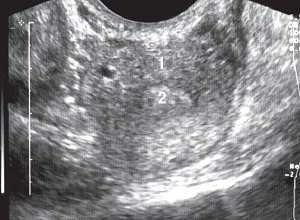

Выполненные нами исследования показали, что одной из основных особенностей однорогой матки являлось уменьшение ее ширины (рис. 1). Ее ширина колебалась от 3,4 до 4,2 см, составляя в среднем 3,8 см, в то время как в норме она варьировалась от 4,3 до 6,5 см при среднем ее значении 5,3 см.

Рис. 1. Ширина однорогой матки (3,4 см). Поперечное трансвагинальное сканирование.

1 - матка; 2 - эндометрий.